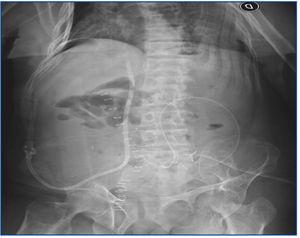

Cuando se dispuso del riñón cadavérico, en el acto quirúrgico, luego de realizado el trasplante, se colocó un catéter en la vena ovárica para realizar hemodiálisis. Se disecó la vena ovárica derecha (dilatada por la obstrucción de la vena ilíaca), se colocó un catéter tunelizado Quinton Permcath® Dual Lumen de 40 cm de longitud y 14,5 French de diámetro, se realizó una sutura de contención en ella y se lo hizo progresar hasta la vena cava inferior. Se constató por radioscopia la colocación y se realizó la tunelización subcutánea en pared abdominal (figura 1 y figura 2). El procedimiento fue bien tolerado. Se comenzó a anticoagular con heparina sódica 6 horas después de la cirugía. Cuarenta y ocho horas después del trasplante renal requirió su primer tratamiento dialítico, que se realizó por el catéter colocado con flujo de bomba de sangre óptimo sin presentar complicaciones, permitiendo realizar el tratamiento dialítico hasta la recuperación de la función del trasplante.

Figura 1. Imagen radiológica que muestra el trayecto del catéter tunelizado, el cual ingresa en vena cava inferior a través de la vena ovárica.